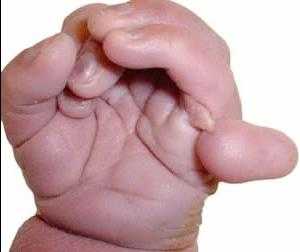

- Пальцы ребенка сжаты в кулак, возможны лишние пальцы

Полидактилия (лишний палец) у ребенка с синдромом Патау

Полидактилия (лишний палец) у ребенка с синдромом ПатауЭта проблема возникает из-за искажения строения позвоночника, у больных детей он часто бывает укороченным. Руки всегда напряжены и сжаты в кулак. Достаточно редко, но были зафиксированы случаи рождения детей с аномалией количества пальцев.

- Патология затрагивает не только кости черепа, но и другие структуры скелета. Например, у детей с синдромом Патау часто наблюдается полидактилия (появление дополнительных пальцев на стопах и кистях) и синдактилия (сращение пальцев).

- в некоторых случаях отмечается увеличение количества пальцев на верхних и нижних конечностях;

Полидактилия (лишний палец) у ребенка с синдромом Патау

- Полидактилия

- Признаки поражения костей, суставов, мышц: сжатая в кулак кисть, полидактилия, сращение пальцев, деформированная стопа.

- Увеличенное количество пальцев рук и ног.